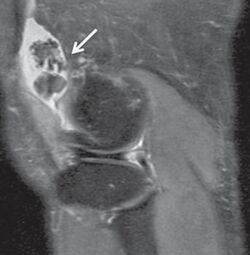

Proton density weighted MRI of a knee with synovial chondromatosis. There are multiple intra-articular loose bodies located in the suprapatellar recess.[5]

Diagnosis is by medical imaging; X-ray, CT scan and MRI.[1] For diagnosis of the TMJ, Cone beam computed tomography (CBCT) can also be useful.[6]